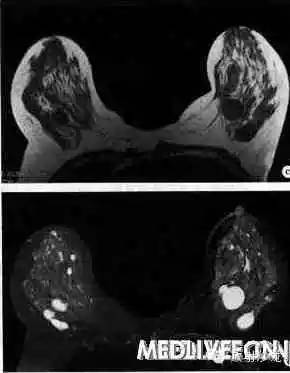

图6-5-1 双乳囊性增生病x线和MRI表现

a.右乳X线头尾位;b.左乳X线头尾位;c.MRI平扫横断面T1WI;d.MRI平扫横断面T2WI。X线表现双乳多发大小不等圆形卵圆形影,边缘光滑、锐利,密度与邻近腺体密度近似;MRI平扫显示双乳腺内多发大小不等肿物,T1WI低信号,T2WI高信号,呈液体信号特征,边缘清晰光滑,内部信号均匀。

当导管、腺泡扩张严重,分泌物潴留时可形成大小不等囊肿,T1WI上呈低信号,T2WI上呈高信号(图6-5-1)。少数囊肿因液体内蛋白含量较高,T1WI上亦呈高信号。囊肿一般不强化,少数囊肿如有破裂或感染时,其囊壁可有强化。